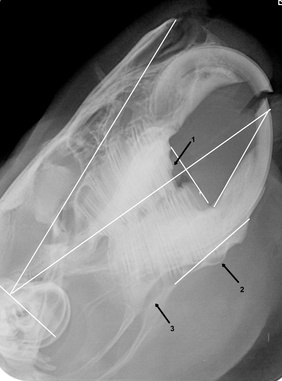

Röntgenbild eines Kaninchenkopfes.

Um die Zahnveränderungen des Tieres objektiv beurteilen zu können, zeichnen wir in jedes Röntgenbild eines zahnkranken Kaninchens die Referenzlinien nach Boehmer und Crossley ein (weiße Linien). In diesem Fall erkennen wir die folgenden krankhaften Veränderungen:

Mehrere Zahnwurzeln im Oberkiefer sind über die obere Linie hinausgewachsen (sogenanntes retrogrades Wurzelwachstum). Dies entsteht durch unzureichende Abnutzung der Zähne beim Kauen, meist aufgrund falscher Fütterung.

Die Stiftzähne dieses Tieres sind viel zu lang. Als Stiftzähne bezeichnet man zwei kleine Zähne, die sich hinter den Oberkieferschneidezähnen befinden. Wenn sie ordentlich abgenutzt sind, dürfen sie kaum über den Saum des Zahnfleischs hinaus sichtbar sein.

Diese Zahnwurzel ist krankhaft verändert.

Diese Zahnwurzel ist ebenfalls krankhaft verändert.

Siehe Punkt 1. Auch hier hat die Zahnwurzel die Höhe der Referenzlinie überschritten = retrogrades Wurzelwachstum. Die Zahnwurzel ist durch den Knochen des Unterkiefers gebrochen.